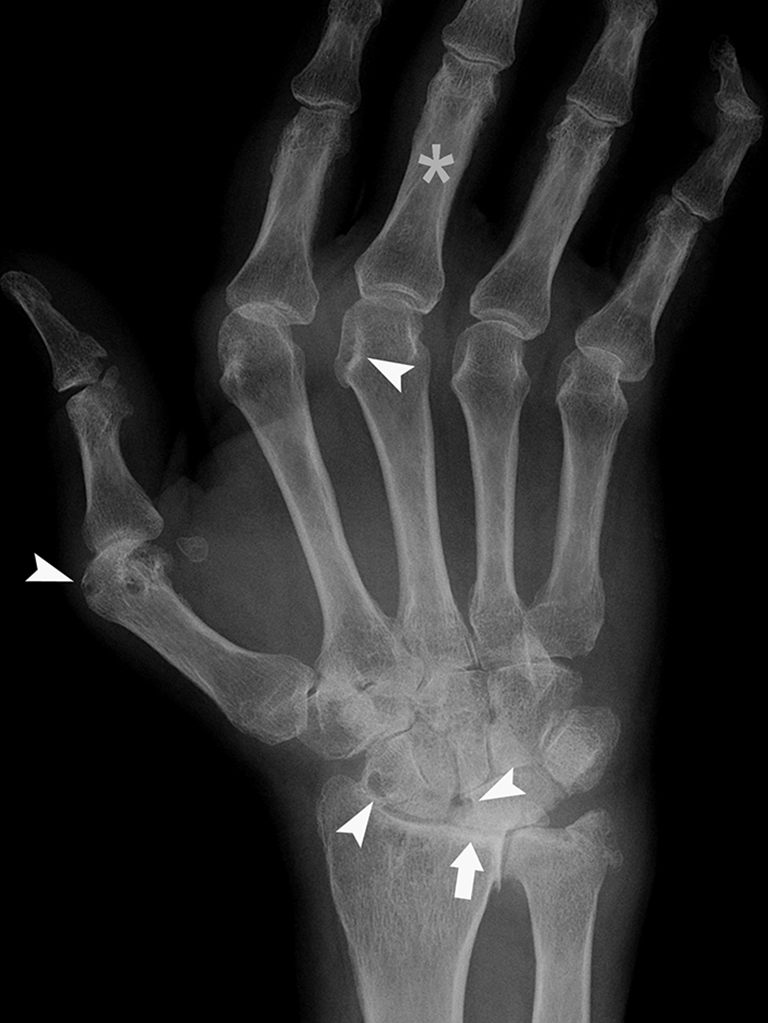

Fig. 81.1. Polyarthrite rhumatoïde.

Radiographie de face du poignet et de la main montrant des pincements des interlignes radiocarpien (tête flèche), des érosions du bord radial des têtes des métacarpiens et des os du carpe (têtes de flèches) et une déviation des doigts (« coup de vent » ulnaire) (*).

Source : CERF, CNEBMN, 2022.

A. Radiographies (figure 81.1)

Les lésions élémentaires à rechercher sont :

- une tuméfaction synoviale ;

- une déminéralisation péri-articulaire ;

- un pincement diffus de l’interligne articulaire ;

- des encoches ou érosions osseuses marginales (aux zones de réflexion synoviale) ;

- une déviation/luxation secondaire à l’atteinte capsulo-ligamentaire :

- sur la main : attitude en « coup de vent » ulnaire ;

- l’absence d’ostéophyte.

À la phase de début, les signes se limitent à la tuméfaction synoviale (arthrite ou ténosynovite) et à une déminéralisation péri-articulaire. Il n’y a pas ou peu d’érosion et pas de pincement. Les radiographies initiales serviront de base pour surveiller l’évolution de la maladie.

Aux mains, les lésions affectent typiquement, de façon bilatérale et symétrique, l’ensemble des articulations métacarpophalangiennes et, de façon souvent plus modérée, les articulations interphalangiennes proximales. Au début, les érosions marginales sont à rechercher sur le bord radial de la tête des 2e et 3e métacarpiens.